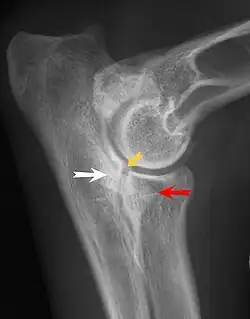

- Heupdysplasie